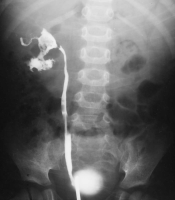

Die Abbildungen zeigen die "stumme" rechtsseitige Niere im AUR sowie die retrograde Sondierung der rechten Niere bei dem Dreijährigen (Abbildung 18).

Die operative Freilegung ergab eine deutlich vergrößerte, narbig umgewandelte Niere. Die histologische Diagnose der entfernten Niere lautete zunächst Urogenitaltuberkulose. Eingehendere Untersuchungen korrigierten dieses Ergebnis. Es bestätigte sich eine XGP. Anhand dieser Beobachtung zeigt sich die Schwierigkeit der Differentialdiagnose bei der XGP (Urogenitaltuberkulose / Tumor) (Abbildung 19).

Beispielhaft die bildgebende Diagnostik und das Organpräparat bei einem Patienten mit XGP (Abbildung 21). Hier führte das intraoperative Schnellschnittergebnis Tumor zur Nephrektomie.